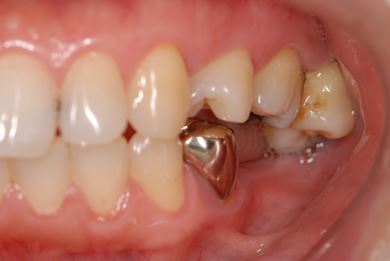

インプラントの症例写真 IMPLANT

インプラント治療+セラミック治療

| 主訴 | 前歯や、下の奥など、何本か気になる歯がある。 | ||||||||||||||||||||||||||||||||

| 治療方針 | インプラント治療により、機能的・審美的回復を行う。 | ||||||||||||||||||||||||||||||||

| 治療内容 | インプラント2本、メタルボンドセラミッククラウン4本、ジルコニアフレームオールセラミッククラウン1本(オールセラミック用土台1本) | ||||||||||||||||||||||||||||||||